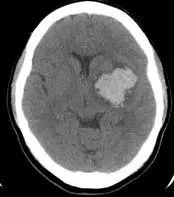

本題影像與上題相同(承上題),為非對比軸切面腦部 CT,顯示右側基底核(殼核 putamen)區均質高密度病灶,特徵如下:

- 高密度病灶:右側基底核區橢圓形均質高密度出血灶,符合急性腦內出血(密度約 50–70 HU)

- 深部中央型出血:病灶位置深部居中,典型高血壓性穿通動脈破裂部位

- 無明顯血管異常徵兆:影像中無明顯動靜脈畸形(AVM)的流空效應(flow voids)、無早期靜脈引流、無鈣化斑、無腫瘤相關徵象

- 臨床背景強烈支持高血壓性出血:56 歲、長期高血壓,深部出血,無外傷史

基於以上影像及臨床背景,診斷已十分明確,不需額外血管攝影即可確診並進行治療。